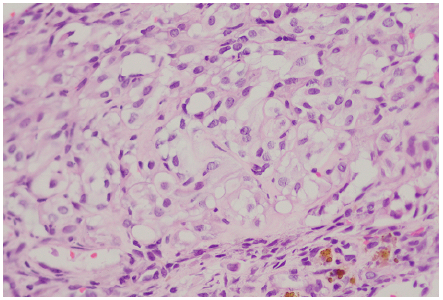

Histopathological analysis revealed a lesion composed of nests of clear cell (Figure 6) surrounded by mixed inflammatory infiltrate without clear chondroid differentiation, findings that raised suspicion of metastatic carcinoma, melanoma, and clear cell chondrosarcoma. Clinically, there were no lesions at other sites where metastasis was suspected. An immunohistochemistry study was performed, finding reactivity for S100 (Figures 7 and 8) with negativity for cytokeratins (AE1AE3), anti-endomysial antibodies (EMA), and me-lanocytic markers HMB45, Melan A, and SOX10. These findings were consistent with clear cell chondrosarcoma with negative tumor margins.

Figure 6 Histopathological analysis showing nests of clear cells.